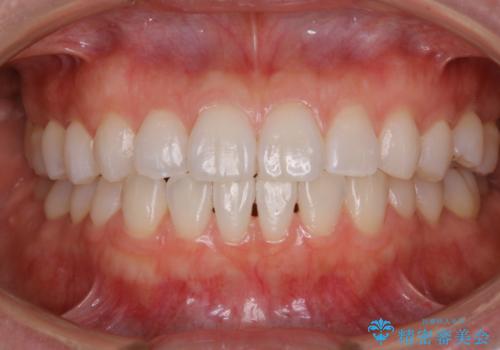

PMTCで清潔感ある口元に

担当医 歯科衛生士